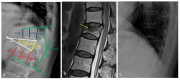

(1) Background: Bisphosphonate treatment failure is one of the most difficult clinical problems for patients with osteoporosis. This study aimed to analyze the incidence of bisphosphonate treatment failure, associated radiological factors, and effect of fracture healing in postmenopausal women with osteoporotic vertebral fractures (OVFs). (2) Methods: A total of 300 postmenopausal patients with OVFs who were prescribed bisphosphonate were retrospectively analyzed and divided into two groups according to the treatment response: response (n = 116) and non-response (n = 184) groups. The radiological factors and the morphological patterns of OVFs were included in this study. (3) Results: The initial BMD values of the spine and femur in the non-response group were significantly lower than those in the response group (all Ps < 0.001). The initial BMD value of the spine (odd ratio = 1.962) and the fracture risk assessment tool (FRAX) hip (odd ratio = 1.32) showed statistical significance in logistic regression analysis, respectively (all Ps < 0.001). (4) Conclusions: The bisphosphonate non-responder group showed a greater decrease in BMD over time than the responder group. The initial BMD value of the spine and the FRAX hip could be considered radiological factors influencing bisphosphonate non-response in the postmenopausal patients with OVFs. The failure of bisphosphonate treatment for osteoporosis has a possible negative on the fracture healing process in OVFs.

Figures